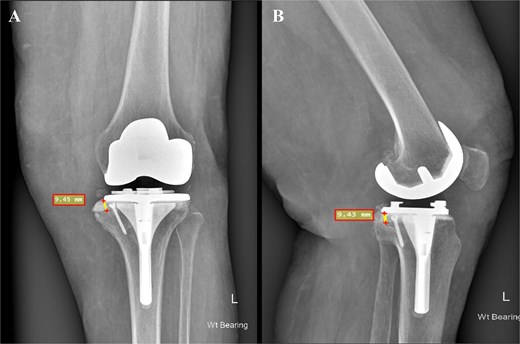

An 80-year-old woman presented with severe left knee pain, disability, and recurrent swelling. X-rays showed advanced osteoarthritis (Kellgren-Lawrence stage IV) with joint space narrowing, varus deformity, and a large medial tibial plateau defect (Fig. 1). The potential bone defect on the medial plateau, which could result in an unsupported region of the tibial component, was identified and highlighted in orange on the pre-operative templating plan. Additionally, a 15.5° varus deformity in the alignment of the native knee was observed (Fig. 2). Patient-specific, 3D-printed surgical guides (Zimmer Biomet), created from MRI-based models, were used for precise femoral and tibial resections.

Preoperative face (A) and profile (B) X-rays showing end-stage knee arthritis with varus deformity and severe collision between the medial femoral and tibial condyles.